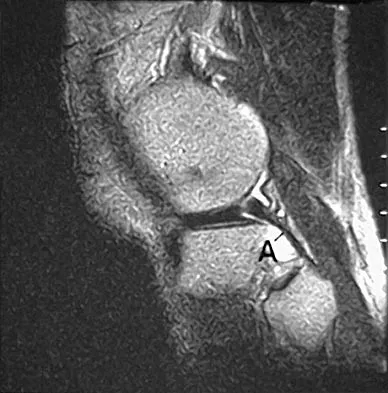

Question 77

The primary function of structure "A" in Figure 29 is to limit

Explanation